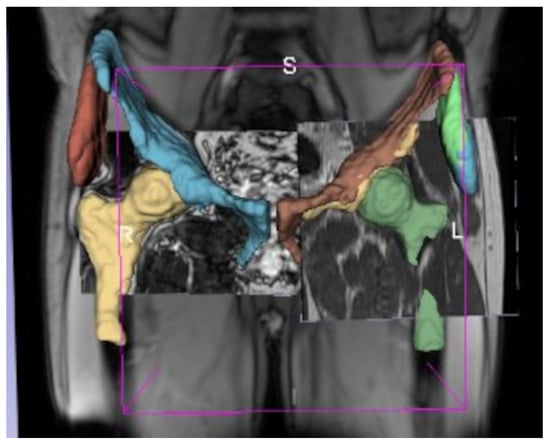

For each subject, the segmented structures were merged into a single composite segmentation using the Simultaneous Truth and Performance Level Estimation (STAPLE) algorithm [24] to increase robustness and minimize noise from automated outputs (Figure 3). Final segmentations were visually reviewed and quality-checked by a musculoskeletal radiologist (I.K., >10 years of experience).

Figure 3. Illustration of the STAPLE algorithm combining three distinct segmentations with varying fields of view to generate a consensus segmentation of four ROIs. By probabilistically weighting each input segmentation, STAPLE improves accuracy and robustness of the final segmentation output. S, superior; L, left; R, right.